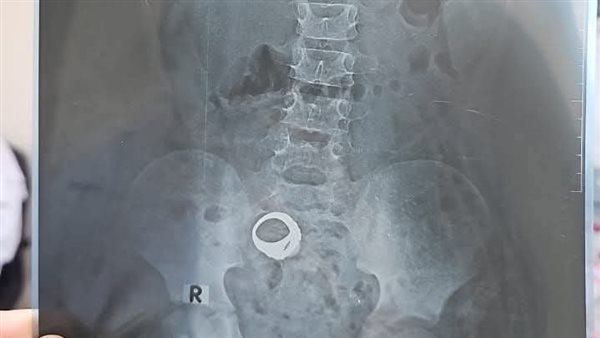

وأكدت إدارة المستشفى أنه ردا على ما تم تداوله على بعض صفحات التواصل الاجتماعي بشأن عودة الطفل معاذ عمار ياسر إلى المستشفى نحيطكم علما بأن الحالة من قرية واقد، وتم الكشف عليها، وتم طلب الأشعة اللازمة.

وتابع البيان: وقامت الأم بعمل الأشعة وتركتها ولم تقم بالذهاب مرة أخرى للعياده لمتابعة الحالة، ومن هنا نحيطكم علما أنه تم التواصل مع بعض الأهالى بقرية واقد للتعرف على الحالة، ونحيطكم علمًا بأن هذه الحالات ليست حالات طارئة ويمكن متابعتها بالعيادة الخارجية بالمستشفى.

وشهدت موقع التواصل الاجتماعي "فيسبوك" حالة من الجدل عقب انتشار دعوات تطالب الأم التي ذهبت بابنها الصغير إلى مستشفى كوم حمادة بعد ما اشتكى من مغص شديد، وقام الأطباء بتشخيص الحالة بتلبك معوي وخرج الطفل مع والدته عقب إجراء الكشف.

وأكد رواد ومستخدمو مواقع التواصل الاجتماعي عبر موقع "فيسبوك" أنه بعد خروج الطفل من المستشفى أظهرت الأشعة وجود خاتم داخل بطن الطفل، لذلك انتشرت الدعوات العاجلة لأي شخص يعرف الطفل أو أسرته أن يتواصل فورًا مع المستشفى أو يذهبوا به سريعًا.